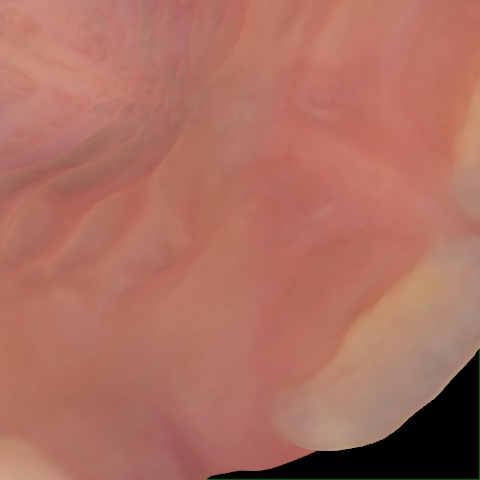

NHD39163

Annotated as "Good"

Original Image Rendering Image